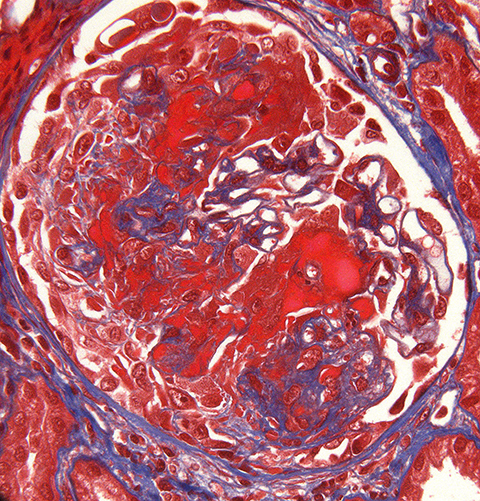

Necrotizing and cellular crescentic glomerulonephritis